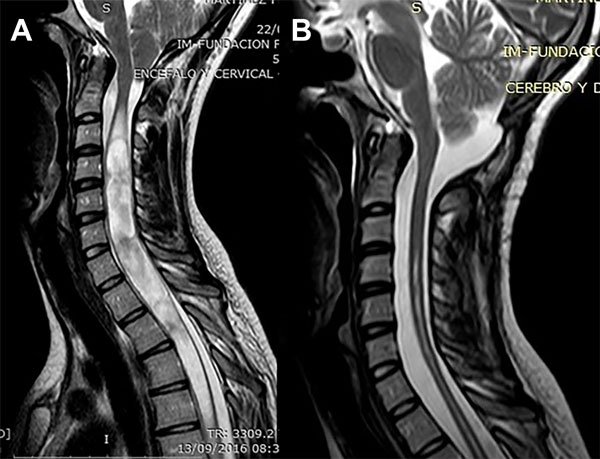

Una paciente de 23 años de edad consultó por parestesias y adormecimiento en ambas manos de 9 meses de evolución sin una progresión clara. El examen neurológico sólo mostró una disminución de la sensibilidad táctil y dolorosa en los extremos de los dedos de ambas manos. La RM mostró un descenso amigdalino de 17,8 mm y una SM entre C3 y T12 con ocupación completa del canal cervical (Figura 4A). La RM en contraste de fase mostró a nivel de la unión occípito-cervical una velocidad de circulación del LCR de 6,6 cm/segundo. Fue llevada a cirugía y se le realizó una descompresión cráneo espinal y duraplastia con periostio. Luego de una evolución postoperatoria satisfactoria fue dada de alta a las 96 horas. A los 3 meses los síntomas previos remitieron. En la RM de control la SM había desaparecido (sólo persistía una cavidad residual) (Figura 4B) y la velocidad de circulación del LCR se había normalizado a 3 cm/seg. En su último control, 6 años después, la mejoría clínica e imagenológica era total.

Figura 4: Caso 2. A: RM de columna cervical en plano sagital ponderada en T2 que muestra una siringomielia cervicodorsal extensa con ocupación completa del canal. B: RM de columna cervical en plano sagital ponderada en T2 postoperatoria que muestra la resolución de la siringomielia.